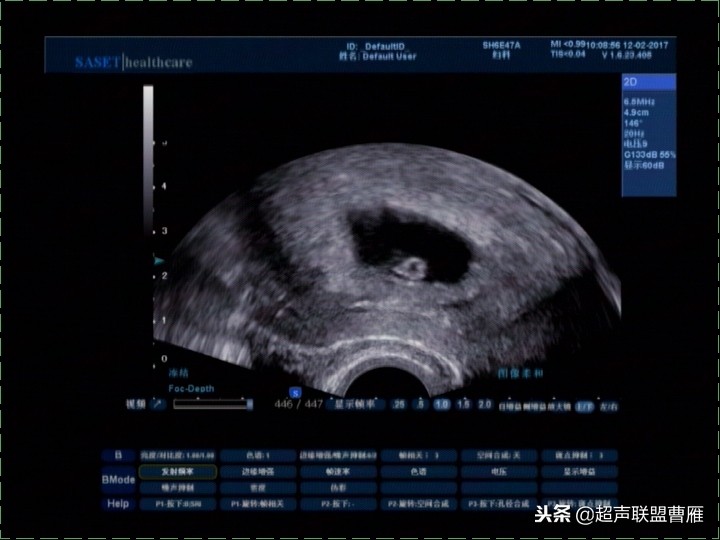

卵黄囊消失